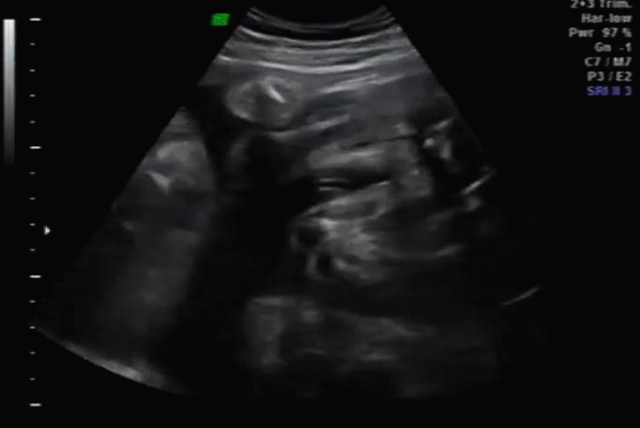

임신 30주 초음파 검사

30주 차! 다행히? 다시 성별반전은 없는 것 같아요~ 허벅지 뼈? 길이 봐주시면서 스쳐갔는데 다리사이에 아무것도 보이지 않네요~

입체 초음파 사진은 항상 만족스러워요! 사진 보면 벌써 태어난 아기처럼 어찌 이리 이목구비 뚜렷하고 아이 얼굴이 선명하게 잘 보이는지~ 제아이라 이렇게 사랑스러운 걸까요~? ㅋㅋㅋ